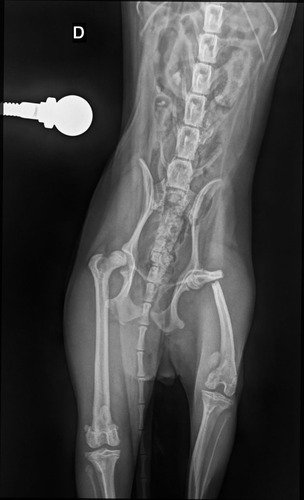

minha cachorrinha Mandy é uma shitzu de 7 meses e ela além de ser mto sapeca e agitada, ela já tinha quebrado o braço um mês atrás 🥲 não deu duas semanas ela fraturou o fêmur brincando com nosso outro cachorro Billy

vou colocar aqui em anexo todo o laudo dela